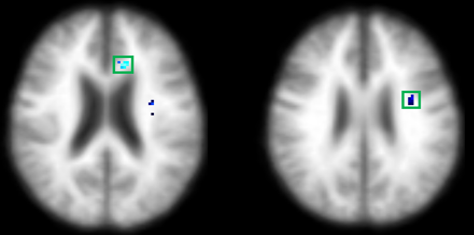

수면무호흡증에 따른 뇌구조 변화

| ▲호전군 |

호전군에서는 시각기억 경로의 회복(노란색)을 확인했으며, 발생군과 지속군에서는 시각기억 관련된 부위의 뇌손상(파란색을) 확인할 수 있다.